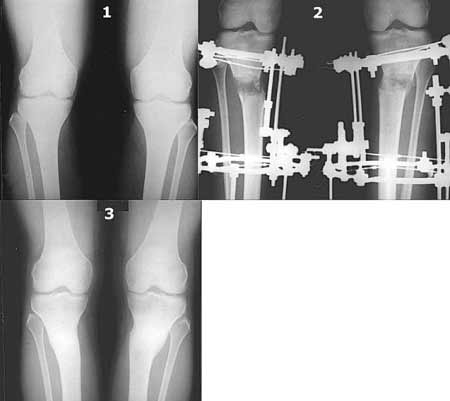

Вот ещё картинки, которые отправлял в Ортопод. Коррекция кривизны и удлинение на 3 см.

Теперь насчет операции, Александр успешно применил более практичный метод, интрамедуллярный штифт для фиксации высокой остеотомии большеберцовой кости в косметологической практике, где для лечения деформации конечности традиционно применялись аппараты внешной фиксации (с удлинением и без) или различные боковые пластины.

Без сомнения, этот почти закрытый (косметологический) метод имеет преимущества перед традиционными, из-за возможности раннего восстановления с ранними нагрузками, когда нашему знаменитому хоккейсту Детроитского Red Wings Steve Yzerman после остеотомии с применением Pudu plate и аллокостью для восстановления потребовалось целый хоккейный сезон.